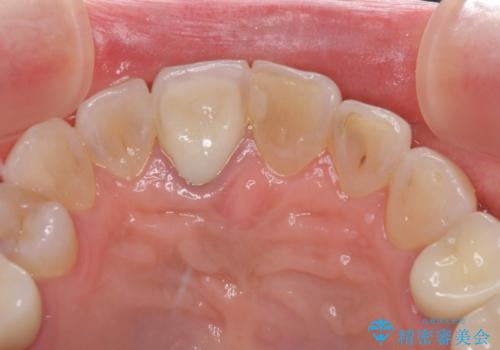

金属を全てセラミックに メタルフリー治療

上下奥歯の抜歯を同時期に行わず、下顎の治療を終えてから上顎を抜歯して治療を進めたため、1年ほどの期間を要しました。

口の中を一切気にしなくて良くなり、患者様には大変満足していただきました。